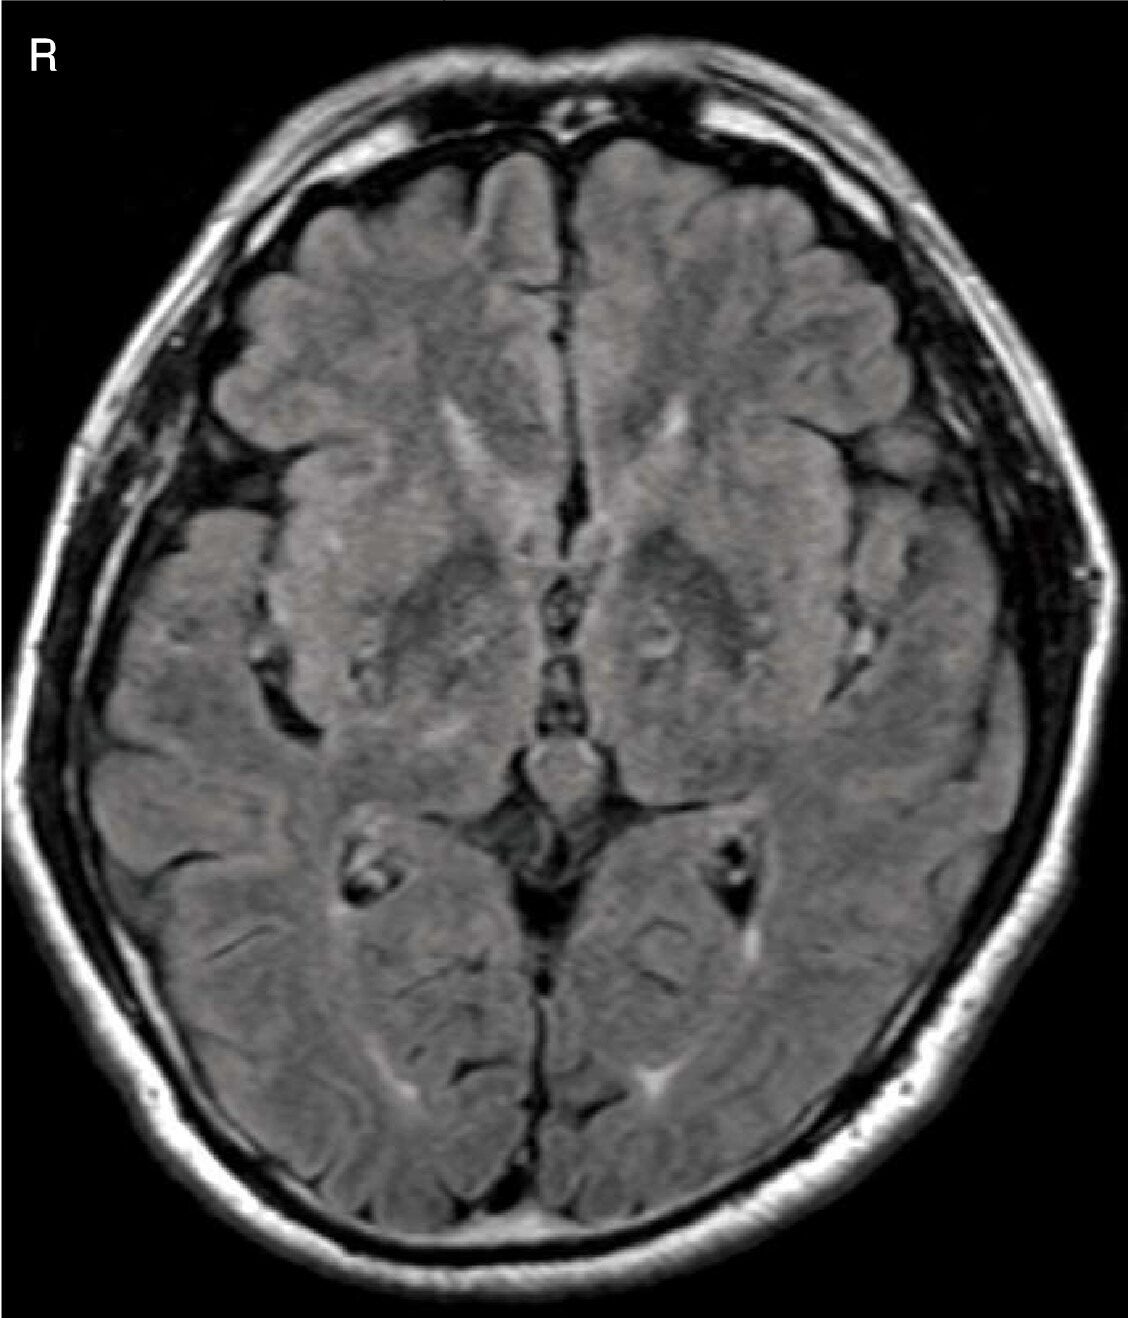

急性期脳梗塞の頭部MRIのFLAIR像(別冊No.4A)及び拡散強調像(別冊No.4B)を別に示す。病変の部位はどれか。